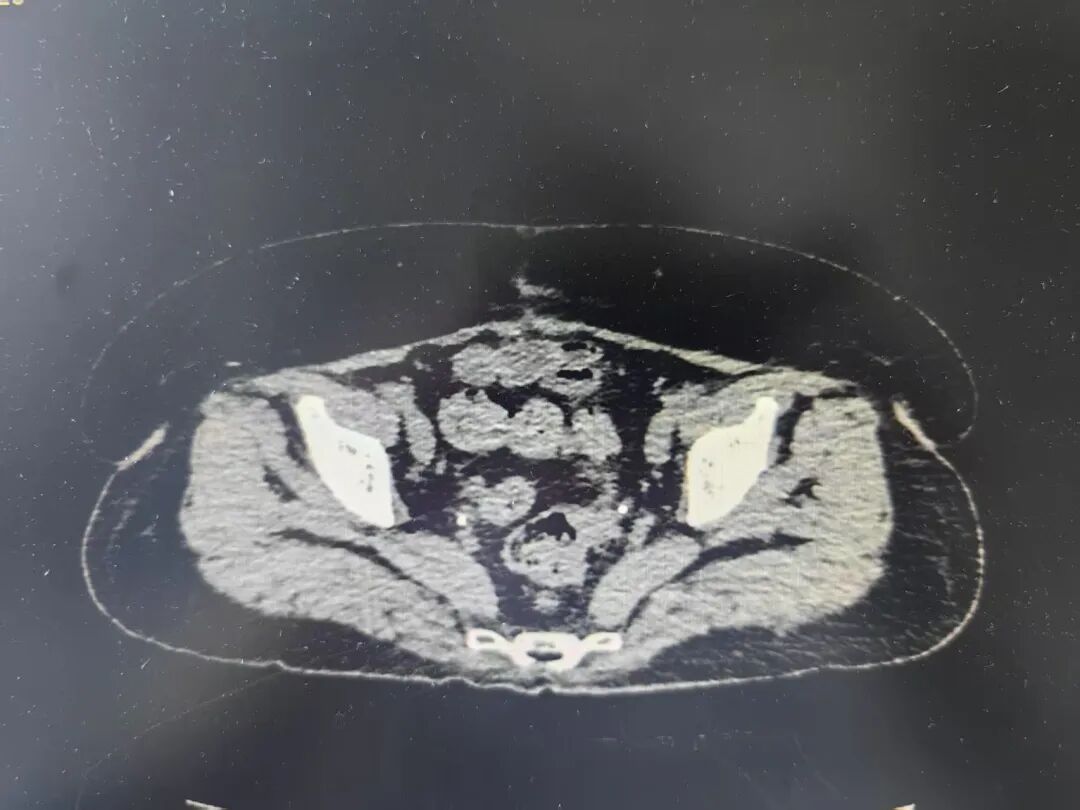

卵巢癌被称为“妇癌之王” 是妇科三大恶性肿瘤之一 可发生于任何年龄 早期症状隐蔽 晚期病例 缺乏有效的治疗手段 致死率居妇科恶性肿瘤的首位 53岁的张女士便不幸遭遇了这一“沉默杀手”。因腹痛、排便困难,来我院就诊时,CT检查发现卵巢肿瘤,强烈提示恶性可能,并存在广泛侵犯。 术前CT显示 因患者病情十分复杂,妇科专家团队立即启动多学科联合诊疗(MDT),综合研判认为,高度疑似晚期卵巢癌。考虑到立即手术难以实现满意的肿瘤细胞减灭,经患者及家属同意后,为其先行腹腔镜探查,获取病理诊断,确诊为:(腹膜、大网膜、肠系膜结节)转移性癌,符合卵巢浆液性癌来源,分期IIIC期。并制定2-3个疗程的新辅助化疗方案,为后续手术治疗创造有利条件。 恰逢重要契机,优质资源无缝对接: 在张女士进行手术治疗准备期间,时任珠海市人民医院副院长刘木彪率队莅临我院开展指导。珠海专家团队在详细了解到张女士的病情后,提出了进一步的治疗方案。 经过充分的前期准备并严格评估新辅助化疗效果,在珠海市人民医院妇科朱定军主任的指导下,我院妇科实施了剖腹探查术,成功减灭肿瘤细胞。术后,张女士继续接受规范化疗,三个月后,CT复查显示:盆腹腔未见病灶复发,肿瘤标记物显著下降。目前治疗仍在顺利进行中。 术后复查CT显示 张女士的经历揭示关键信息: 定期体检至关重要: 建议25岁以上的女性定期进行妇科检查及盆腔超声检查。 我院妇科与珠海市人民医院妇科建立了专科联盟合作关系。在此合作框架下,双方积极开展交流与协作,珠海市人民医院的妇科专家团队不定期前往我院开展门诊坐诊、教学查房、手术指导等工作,为贵州航天医院妇科肿瘤诊疗能力提升注入强劲动力。 贵州航天医院妇科 专家简介 邓桂林 妇科、耳鼻咽喉科党支部书记,妇科主任,主任医师 临床擅长:擅长妇科常见病、多发病的诊治,主攻方向妇科肿瘤,熟练掌握宫腔镜子宫肌瘤切除术、腹腔镜下子宫切除术、腹腔镜下早期宫颈癌根治术、子宫内膜癌分期手术、卵巢癌全面分期手术以及阴式手术等手术。 从事妇科专业医疗、教学及科研近20年,曾先后前往首都医科大学附属复兴医院、广州佛山市第一人民医院、重庆医科大学第一附属医院、遵义医科大学进修培训妇科内镜,通过CSCCP全国阴道镜规范化系列培训并获得GESEA证书;主持航天科工集团课题及遵义市科技局科研课题各1项,以第一作者发表学术论文10篇,参与编著著作2本,获专利6项。是中国初级卫生保健基金会妇科内分泌与辅助生殖专业委员会委员,中国优生优育协会妇产科专业委员会委员,中国医药教育协会更年期医学教育专业委员会委员,《妇儿健康导刊》杂志编委,中国中医药信息学会科学普及及分会第二届理事会理事,贵州省药学会妇产科疾病药物治疗专业委员会委员,贵州省医学会计划生育学分会第二届委员会委员,贵州省中西结合学会第二妇产专业委员会委员,贵州省中西结合学会第二届妇产专业委员会第一届绝经学组委员委员,贵州医科大学附属医院妇科更年期专科联盟委员,遵义市中西医结合学会妇产专业委员会第一届副主任委员,遵义市妇产科学会第一届委员会委员,遵义市妇产科学会妇科肿瘤学分会第一届委员会委员,遵义市预防接种异常反应调查诊断专家。 温小英 妇科主任医师 临床擅长:从事妇产科临床、科研、教学工作近30年,对妇科各类良、恶性肿瘤的开腹手术具有丰富的手术经验,开展腹腔镜及阴式手术10余年,擅长妇科常见疾病诊断治疗,尤其擅长女性生殖道炎症,内分泌疾病等治疗。 主持参与省、市级科研项目多项,发表科研论文10余篇。 卢 韦 妇科副主任医师,硕士研究生 临床擅长:从事妇产科临床、科研、教学工作17年,对妇科常见病,多发病及妇科肿瘤诊治具有丰富的临床经验,尤其擅长宫腹腔镜多种微创手术、阴式手术、妇科肿瘤手术等。 遵义市医学高等专科学校授课教师,亚太生殖大健康协会委员,中国医药教育协会生殖内分泌专业委员会委员,贵州省医学会“健康贵州行动”妇产科巡讲团团员,女性下尿路疾病及盆底功能障碍性疾病及专家联盟委员,中西医结合专家志愿者学会妇产科专业委员会委员;曾多次前往北京首都医科大学附属复兴医院、广州南方医科大学附属第一医院、重庆市妇幼保健院、贵阳市妇幼保健院、贵州医科大学附属医院、遵义医科大学附属医院进修学习及交流;发表国家核心期刊杂志及国家级普刊杂志10余篇,发明实用性专利3项,参与编写妇产科应用教材1部,主持及参与省、市级科研课题2项。 苏远华 妇科副主任医师,硕士研究生 临床擅长:外阴白斑、子宫腺肌病、妇科肿瘤及内分泌等疾病的诊治;手术擅长:腹腔镜、宫腔镜、阴式等微创手术;临床科研方向:外阴白斑及子宫腺肌病。 2009年毕业于遵义医学院临床医学。2009年7月至2012年7月于遵义医科大学附属医院参加妇产科专科医师规范化培训3年并结业。2012年8月至今在遵义市贵州航天医院妇科工作,从事妇科临床工作及教学工作10余年,曾多次评为年终优秀带教老师。2016年4月于北京复兴医院学习宫腹腔镜并取得培训合格资格证书;2018年7月至2019年1月于重庆西南医院进修妇科腹腔镜技术。申报立项及获得资金资助的省级课题1项,参与市级课题研究2项。曾参加遵义市腹腔镜操作技能比赛获得三等奖。发表国家医学论文核心期刊5篇,其中第一作者4篇、专家述评1篇,省级论文3篇;参与编著书籍1本。遵义市高等医科专业学校授课教师;遵义市中西医结合学会妇产科专业委员会第一届秘书;妇科肿瘤学分会第三届委员会青年委员。 贵州航天医院 妇科简介 基本情况 贵州航天医院妇科是集医疗、教学、科研于一体的综合性临床科室,共有医护人员27人,现有正高级职称2人,副高级职称2人,硕士研究生7人,开放床位30张,多次获得医院优秀教学科室、技术创新优秀科室、健康宣教优秀集体等荣誉称号。配备有阴道镜检查仪、阴道B超机、门诊宫腔检查镜、盆底治疗仪、宫颈微波治疗仪、低频脉冲治疗仪、中频脉冲治疗仪、红外线治疗仪以及永磁旋震治疗仪等先进设备。 专科特色 (一)宫腔镜手术 宫腔镜检查术,粘膜下子宫切除术,子宫内膜息肉切除术,子宫内膜切除术,宫腔黏连分离术,宫腔异物取出术,子宫纵膈切除术,宫颈瘢痕妊娠病灶清除术(冷刀,电切均可)。 (二)腹腔镜手术 早期宫颈癌根治术,子宫内膜期全面分期手术,早期卵巢癌全面分期手术,全子宫切除术,子宫肌瘤剔除术,单孔腹腔镜输卵管切除术及卵巢剔除术等妇科良性病变手术。 (三)盆底重建手术:阴式全子宫切除术 子宫脱垂、阴道前后壁合并膀胱及直肠脱垂等盆底脏器脱垂的修补术:经阴道骶棘韧带悬吊术,经腹腔镜子宫(阴道)骶骨悬吊术,针对压力性尿失禁的尿道中段折叠缝合术及TVT-O手术。 (四)外阴整形术 会阴整形术、小阴唇整形术及阴道缩紧术。 诊疗范围 科室业务范围涵盖普通妇科、妇科肿瘤、生殖整复、计划生育、生殖内分泌。 普通妇科:诊治外阴、阴道、宫颈、子宫、附件及盆腔的各种炎症及良性病变。 妇科肿瘤方面:开展经腹及经腹腔镜宫颈癌、子宫内膜癌、卵巢癌手术及术后化学治疗。 生殖整复方面:开展大、小阴唇整形、处女膜修复、阴道缩紧、宫颈成形、输卵管复通。 计划生育方面:保胎、流产、监测排卵、促排卵、上环、取环。 妇科内分泌方面:开展调经、围绝经期的激素替代治疗等,手术途径可行宫腔镜、腹腔镜(含单孔腹腔镜)、宫腹腔镜联合手术等。 门诊开展项目:产后盆底肌康复治疗,宫颈癌三级预防,宫颈炎症微波治疗,无痛宫腔镜,无痛人流,诊刮、取环等宫腔操作。